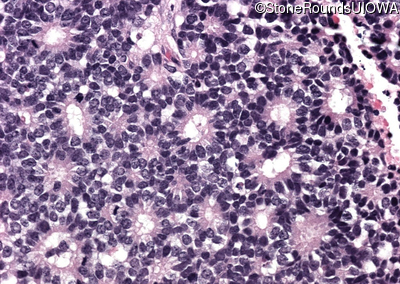

Pathology - Left - -

Exemplar